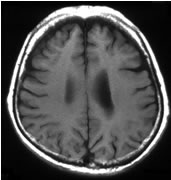

転移性脳腫瘍

近年、ガンマナイフ症例数のほぼ半分を占めています。基本的には1〜10病変未満が良い適応となります。複数の病変であっても、1回の治療ですべてを治療することが可能です。

![]() ![]() |

| ガンマナイフ時 |

| 6ヶ月後 |